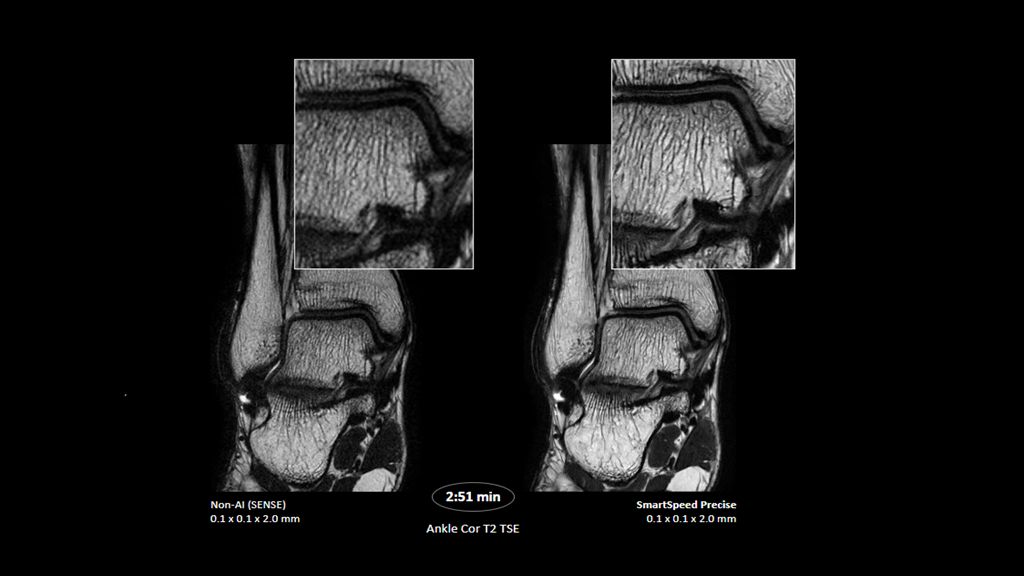

1. Compared to SENSE imaging, with no loss in image quality.

2. Reconstruction technology Compared to conventional (SENSE/ Compressed SENSE, SmartSpeed AI) imaging. Sharpness was evaluated with phantom scanning.